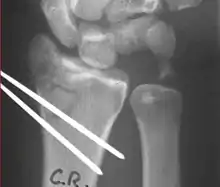

Surgery is generally indicated for displaced or unstable fractures.[18] The techniques of surgical management include open reduction internal fixation (ORIF), external fixation, percutaneous pinning, or some combination of the above. The choice of operative treatment is often determined by the type of fracture, which can be categorized broadly into three groups: partial articular fractures, displaced articular fractures, and metaphyseal unstable extra- or minimal articular fractures.[5]

Surgical options have been shown to be successful in patients with unstable extra-articular or minimal articular distal radius fractures. These options include percutaneous pinning, external fixation, and ORIF using plating. Patients with low functional demand of their wrists can be treated successfully with nonsurgical management; however, in more active and fit patients with fractures that are reducible by closed means, nonbridging external fixation is preferred, as it has less serious complications when compared to other surgical options.[5] The most common complication associated with nonbridging external fixation is pin tract infection, which can be managed with antibiotics and frequent dressing changes, and rarely results in reoperation.[5] The external fixator is placed for 5 to 6 weeks and can be removed in an outpatient setting.[5]

These fractures, although less common, often require surgery in active, healthy patients to address displacement of both the joint and the metaphysis. The two mainstays of treatment are bridging external fixation or ORIF. If reduction can be achieved by closed/percutaneous reduction, then open reduction can generally be avoided. Percutaneous pinning is preferred to plating due to similar clinical and radiological outcomes, as well as lower costs, when compared to plating, despite increased risk of superficial infections.[24] Level of joint restoration, as opposed to surgical technique, has been found to be a better indicator of functional outcomes.[5]